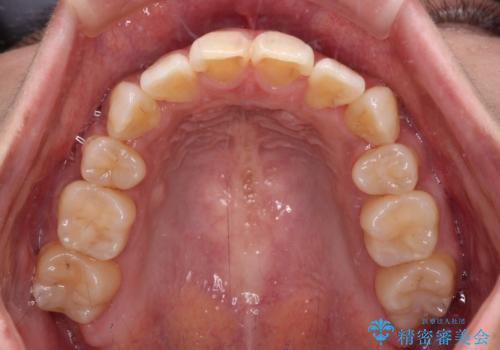

気になる八重歯を目立たない装置で改善 ハーフリンガル矯正

ハーフリンガルでの矯正治療は、表側矯正よりも期間がかかることが多く、抜歯矯正では3年以上かかることも珍しくありません。

デコボコが強い一方で出っ歯ではなかったため、抜歯したスペースを容易に閉じることができ、短期間での治療となりました。